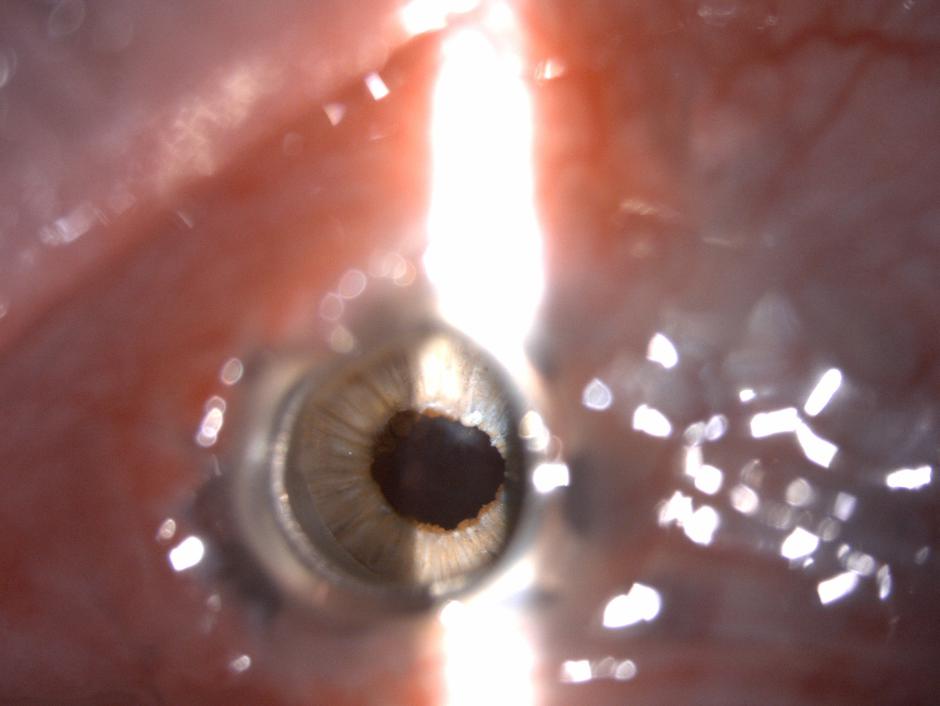

Oko pred posegom | Avtor: UKCLJ UKCLJ

"Bolnik je utrpel poškodbo z apnom pred več kot 20 leti in pri tem popolnoma izgubil vid na obe očesi. Na desnem očesu je imel v nekaj letih po poškodbi dvakrat presajeno roženico, vendar je obakrat prišlo do zavrnitvene reakcije in se je roženica zamotnila," so sporočili iz Univerzitetnega kliničnega centra v Ljubljani, kjer so uspeli bolniku povrniti vid na levem očesu.